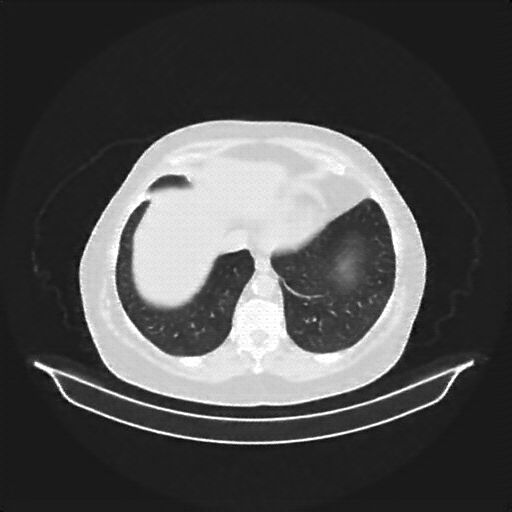

Original NATIVE CT scan (input)

Full window (WL 1023.5, WW 4095 β†’ Low βˆ’1024, High +3071)

Lung window (WL -600, WW 1500 β†’ Low βˆ’1350, High +150)

Mediastinum window (WL 40, WW 400 β†’ Low βˆ’160, High +240)